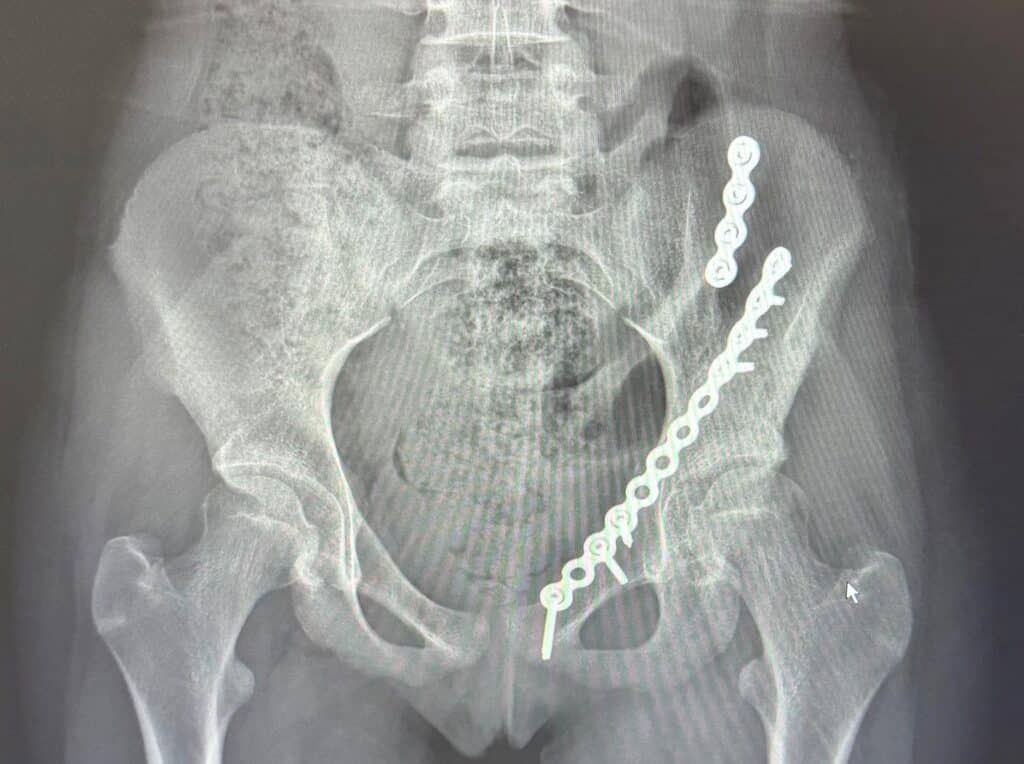

Liv was rushed to the Royal Children’s Hospital in Melbourne, where she faced a long and painful wait for surgery. “I was there for two days waiting for specialist equipment, before undergoing a five-hour operation,” she explains. “I ended up with 10 screws and two plates through two large incisions.”

X-rays post surgery. Image supplied.

“As soon as the

surgeon gave me the

all-clear, I was ready.”

At five and a half weeks post-op, Liv received the green light to begin weight-bearing again. “That was a huge milestone,” she says. “But I also found out I had a small fracture in my tibia and foot, which slowed me down a little. Still, I kept soldiering on, and it resolved itself after a few weeks.

By nine weeks she was back in the saddle. At twelve weeks, she was jumping again.